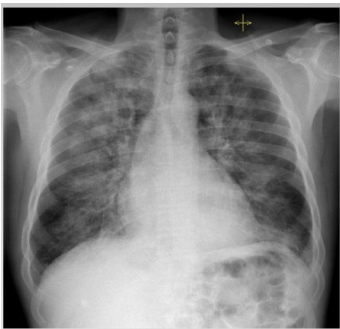

Analise a seguinte imagem.

Considerando a radiografia de tórax anterior, é correto afirmar que